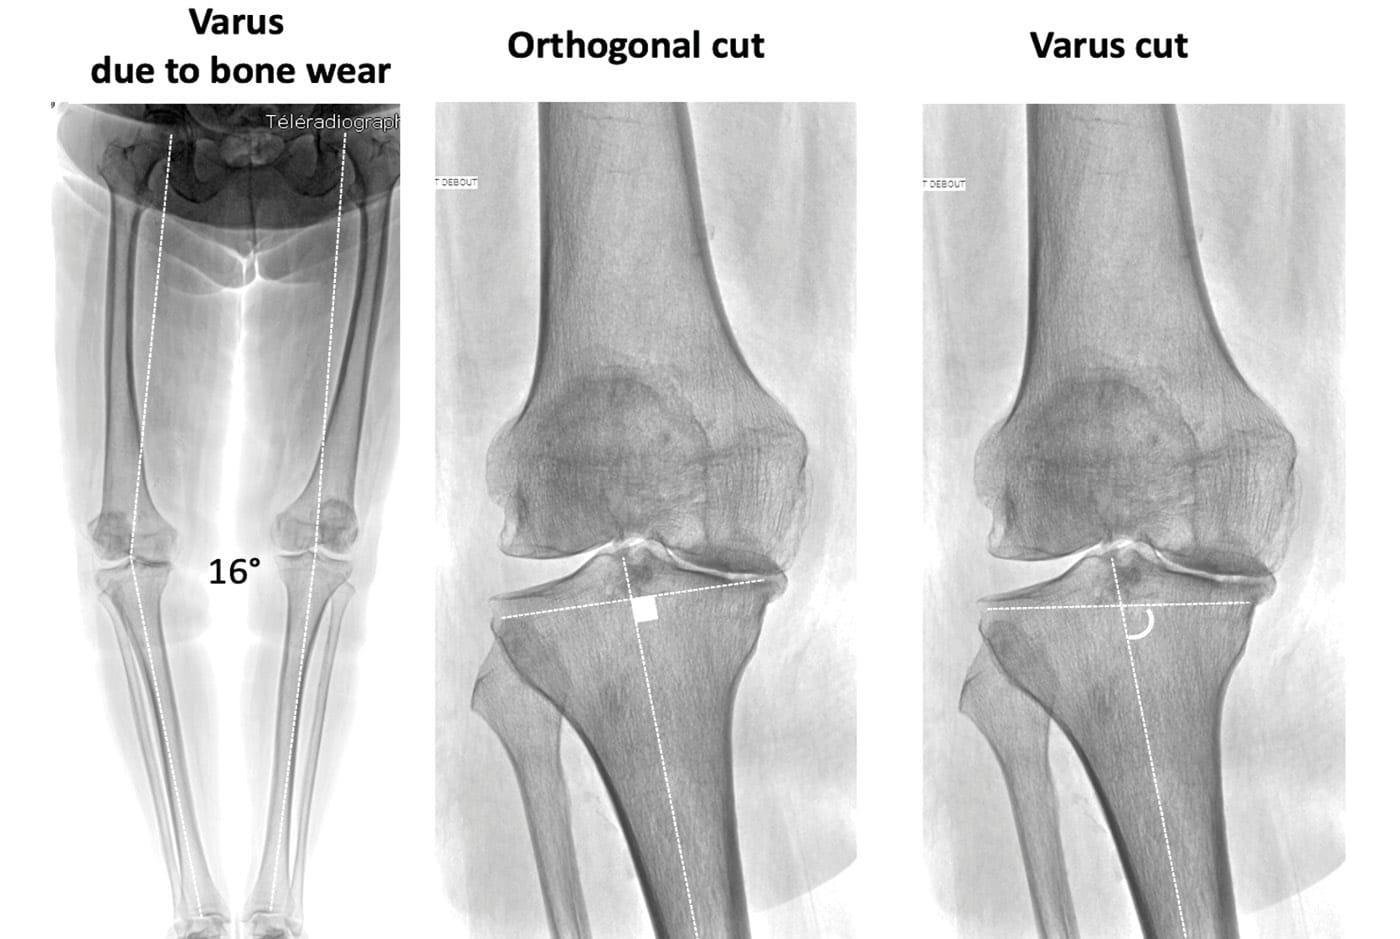

An important advantage of 3D CT planning is that it enables direct visualization of the bone defects, which generally involve only a limited area of the tibial plateau (or more rarely the condyle), and to deduce the native shape of the articular surface by referring to non-damaged areas (Figure 4) [7] Dossett HG, Estrada NA, Swartz GJ, LeFevre GW, Kwasman BG (2014) A randomised controlled trial of kinematically and mechanically aligned total knee replacements: two-year clinical results. Bone Joint J 96-b (7):907-913. . While the femur and tibia are analyzed separately, it is possible to calculate the native femoral and tibial angles, the arithmetic HKA, and to know the precise native phenotype of the patient. All technologies based on preoperative CT analysis provide this advantage, and the success of image-based robotics is due to, among other reasons, this possibility to plan in 3D and to facilitate the kinematic alignment technique [1], Batailler C, Bordes M, Lording T, Nigues A, Servien E, Calliess T, Lustig S (2021) Improved sizing with image-based robotic-assisted system compared to image-free and conventional techniques in medial unicompartmental knee arthroplasty. Bone Joint J 103-b (4):610-618. [14], Huber K, Christen B, Calliess S, Calliess T (2021) True Kinematic Alignment Is Applicable in 44% of Patients Applying Restrictive Indication Criteria-A Retrospective Analysis of 111 TKA Using Robotic Assistance. J Pers Med 11 (7). [19] Morcos MW, Uhuebor D, Vendittoli PA (2023) Overview of the different personalized total knee arthroplasty with robotic assistance, how choosing? Front Surg 10:1120908. .